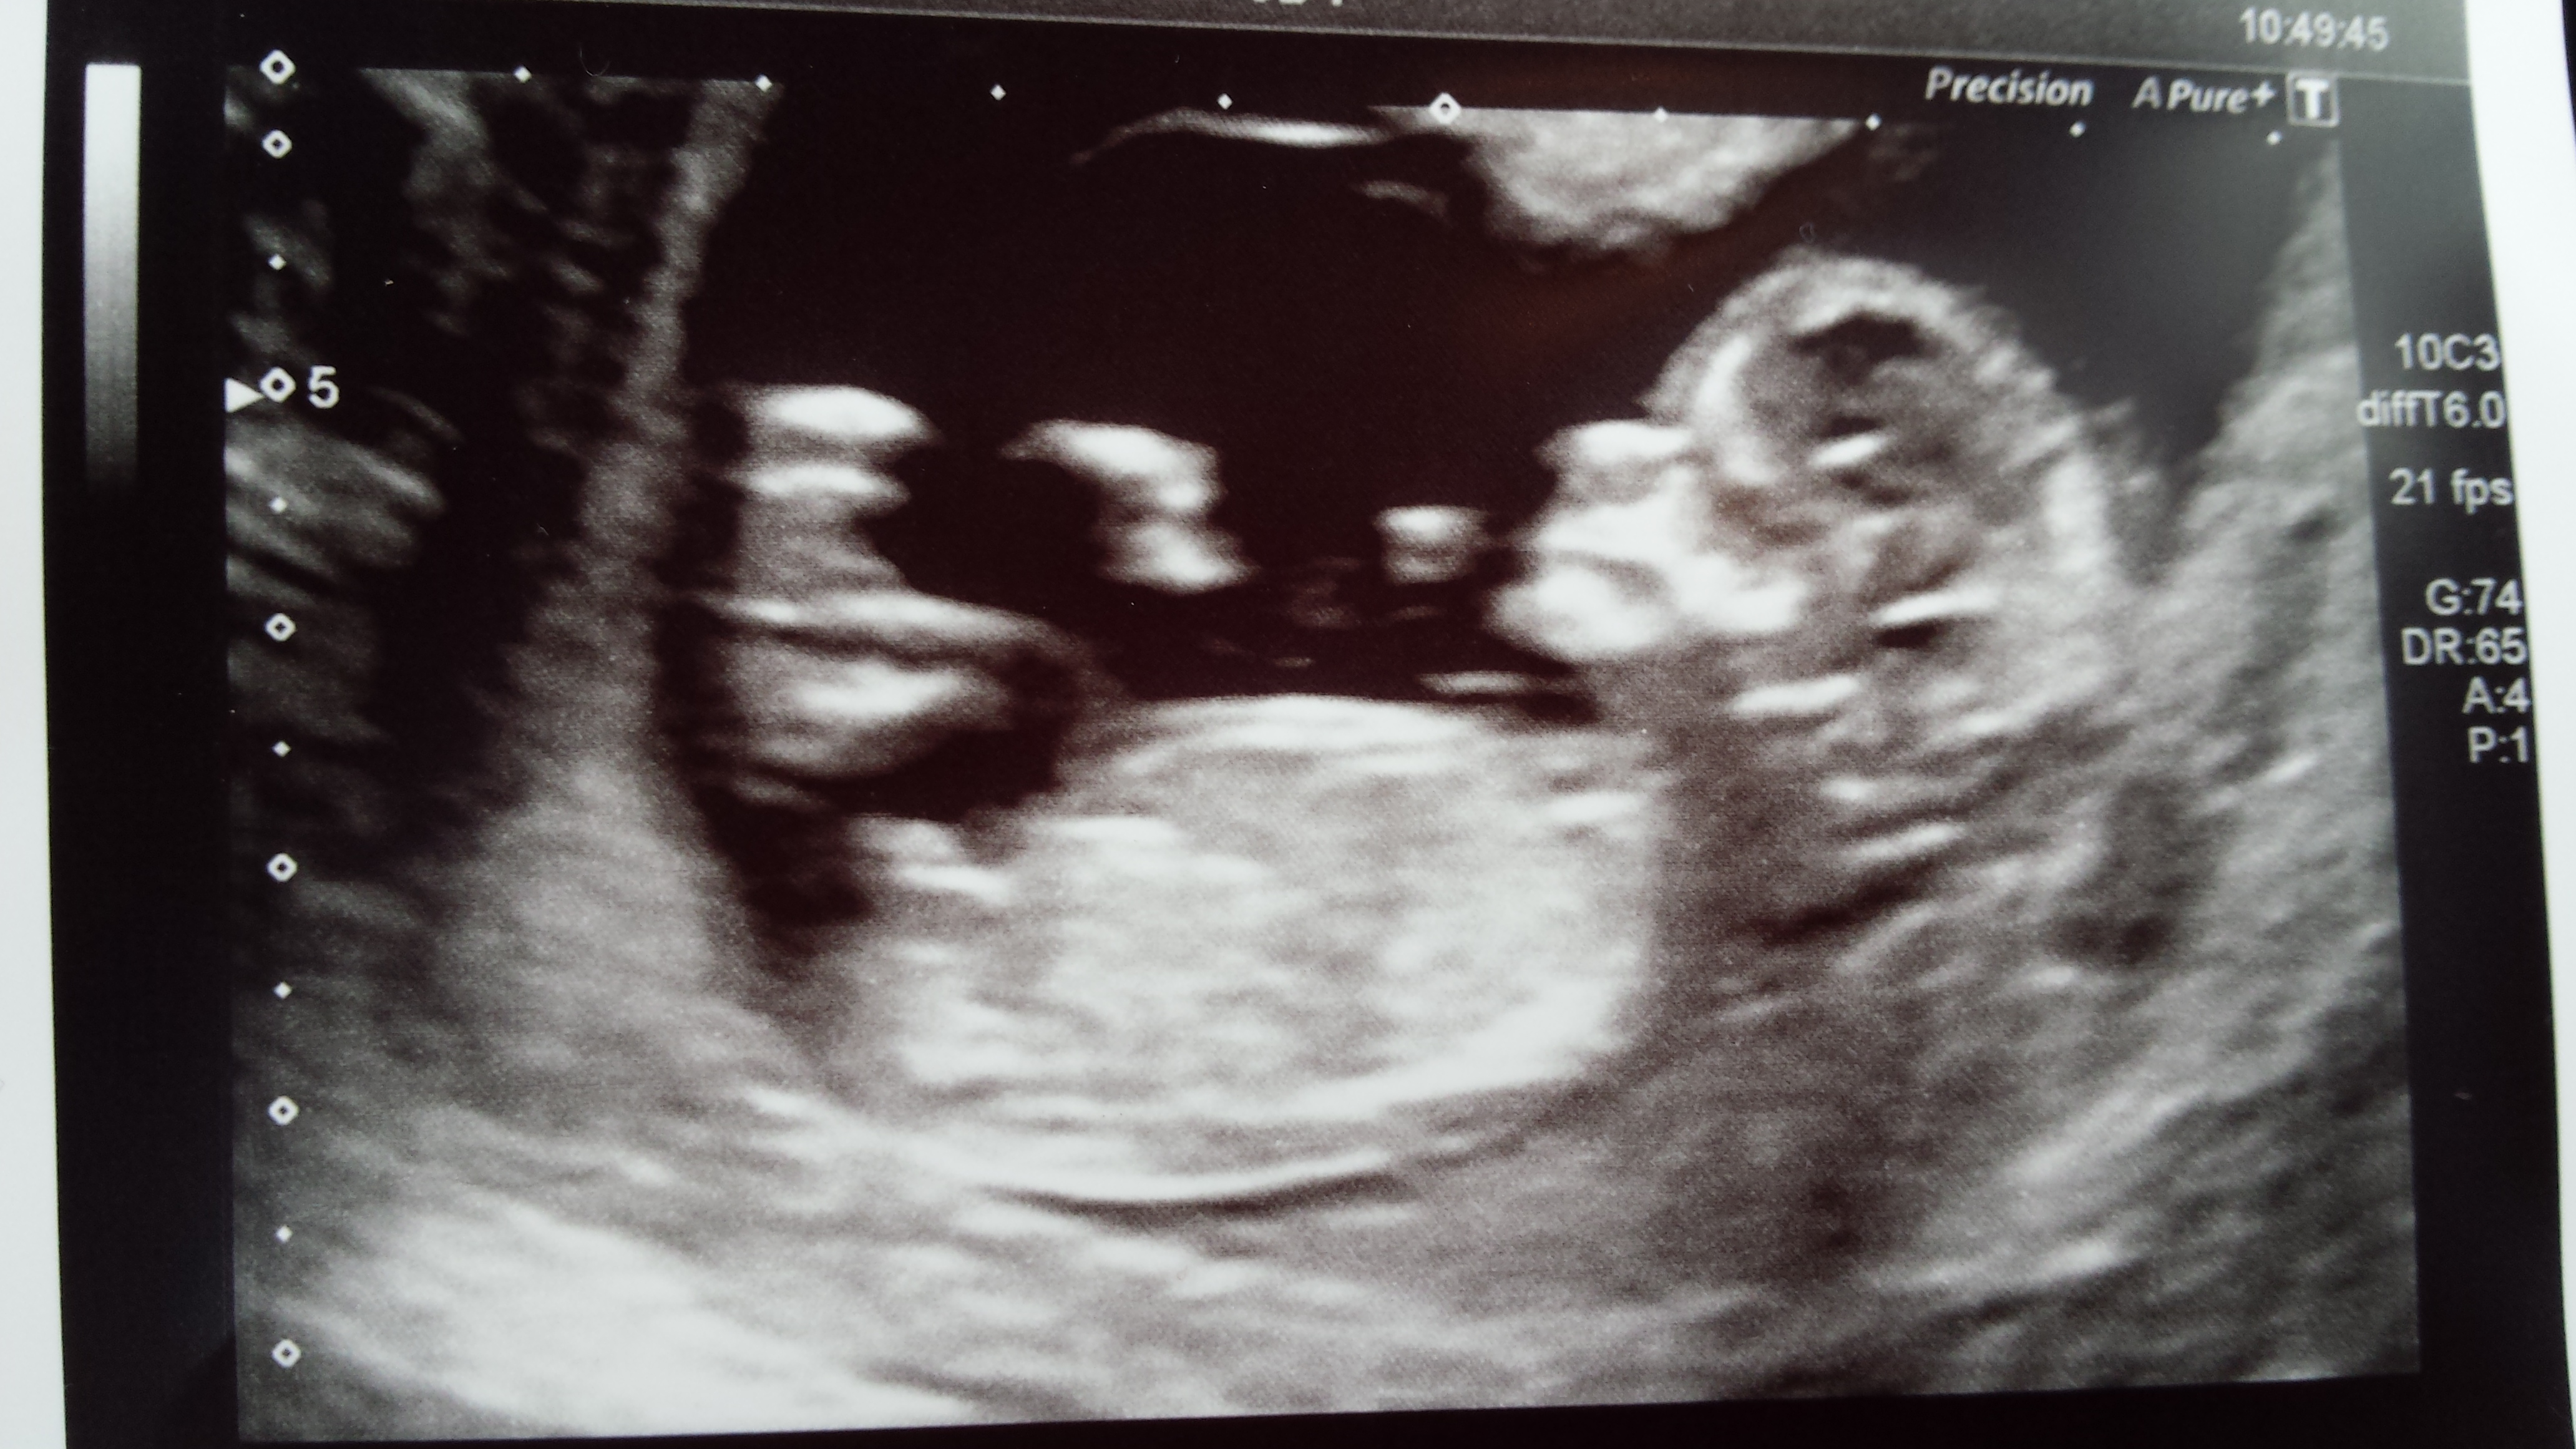

As titleAttachment 21839 says :) boy or girl guesses and reason for your guess x

Hmm the first pic looks boy from the stacked nub but the 2nd looks like a girl from the flat straight nub!! confusing lol. Congrats though, cute baby!

This one is kind of hard... one nub pic looks more girly, but the other looks more boyish.. I think I'm leaning boy, but really unsure.

Looks stacky I guess boy but not so sure on this one x